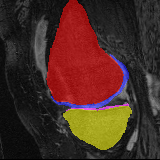

Moving Target Mono-0 Mono-5 DA-1 DA-5 Mono-200 Refer to caption Refer to caption Refer to caption Refer to caption Refer to caption Refer to caption Refer to caption Refer to caption Refer to caption Refer to caption Refer to caption Refer to caption Refer to caption Refer to caption

Figure 2:  Examples of knee MRI registration (top) and brain MRI segmentation (bottom) results. Top: The first two columns are the moving image/segmentation and the target image/segmentation followed by the warped moving images (with deformation grids)/segmentations by different models. Bottom left to right: original image, manual segmentation, and predictions of various models. Mono-i𝑖i and DA-i𝑖i represent the mono- and DA models with i𝑖i manual segmentations respectively.

Knee results: On knee MRIs, our method improves segmentation scores over separately learned networks by about 1.2 and 0.5, and registration scores increase by about 3.1 and 3.0, when training with 5 and 10 manual segmentation respectively. Especially for the challenging cartilage structures, our joint learning boosts segmentation by 1.4 and 0.7, and registration by 5.5 and 5.2 for N=5 and N=10 respectively.

Qualitative results: DA achieves more anatomically consistent registrations than the mono-networks on the knee (Fig. 2) and Brain MRI samples (see supplementary material).